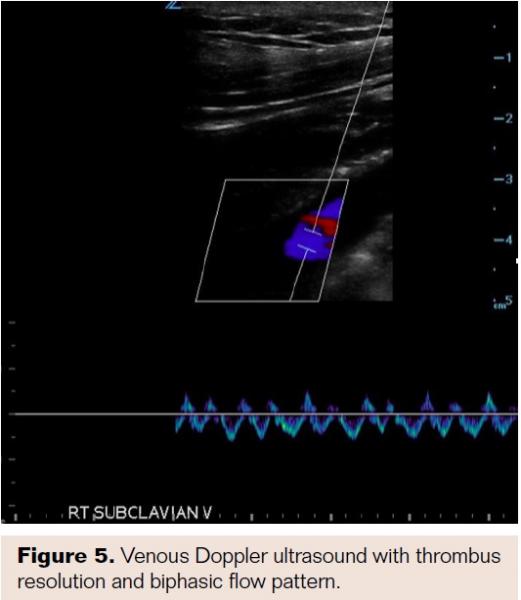

After 12 hours of treatment, the patient noted no further arm pain and improvement in right upper extremity swelling. Repeat venous ultrasound demonstrated no further thrombus in the basilic, axillary, or subclavian veins (Figure 5). Alteplase infusion was discontinued, and EKOS catheter and glidesheath were removed. Full dose intravenous heparin was restarted and the patient bridged to oral anticoagulation with rivaroxaban. An ACE wrap and thromboembolism deterrent hose were used to provide compression and aid in the reduction of edema in the right arm, and the patient was discharged home 48 hours post lytic therapy.